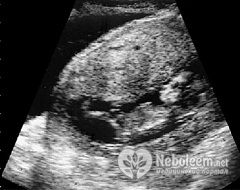

УЗИ на 12 неделе беременности покажет, как сокращаются камеры сердца, а также пол плода. Правда, будущий малыш не всегда показывает свои половые органы во время исследования, скрещивая ножки между собой.

На УЗИ на 12 неделе беременности можно установить пол будущего ребенка. Правда, для этого требуется проведение обследования на современном и высокоточном оборудовании. Кроме того, ультразвуковое исследование уточняет срок беременности, выявляет грубые пороки развития. К этому обследованию приурочен анализ крови на альфа-фетопротеин, который показывает возможность хромосомных аномалий плода. Особенно необходимо его проведение у женщин в возрасте старше 35-40 лет.